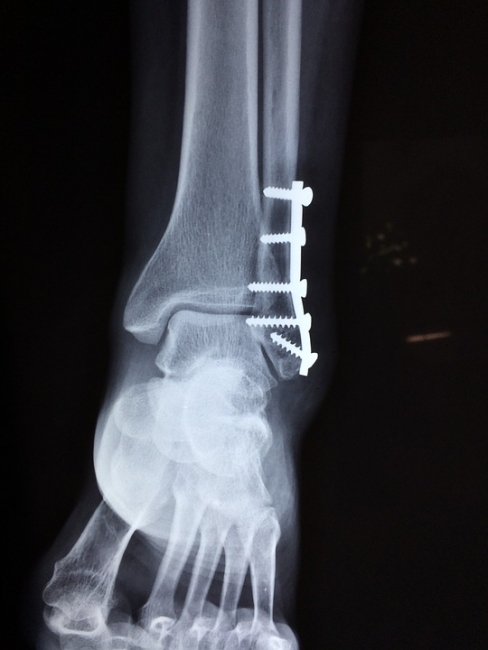

К травматологу нужно обращаться в случае перелома или вывиха, при ушибе мягких тканей и деформации конечностей. Если человека беспокоят частые боли в суставах, мышцах или костях, то также нужно обязательно посетить врача. К травматологу отправляются тогда, когда после ушиба долго не проходит боль, а ткани в месте повреждения изменяют свой цвет. Чем раньше больной человек посетит клинику − тем более результативным и лёгким будет лечение. Часто случается так, что после падения или удара человек не ощущает боли и думает, что помощь врача не требуется. На самом деле лучше сразу посетить его, ведь скрытая травма может представлять огромную опасность.